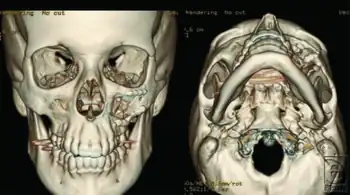

3-D reconstructions, demonstrating anatomic reduction of the zygomaticomaxillary complex fracture with hardware in place at the infraorbital rim

Non-displaced or minimally displaced fractures may be treated conservatively. Open reduction and internal fixation is reserved for cases that are severely angulated or comminuted. The purpose of fixation is to restore the normal appearance of the face. Specific attention is given to the position of the malar eminence and reduction of orbital volume by realigning the zygoma and sphenoid. Failure to correct can result in rotational deformity and increase the volume of the orbit, causing the eye to sink inwards.

Fractures with displacement require surgery consisting of fracture reduction with miniplates, microplates and screws. Gillie's approach is used for depressed zygomatic fractures.[5] The prognosis of tripod fractures is generally good. In some cases there may be persistent post-surgical facial asymmetry, which can require further treatment.[6]